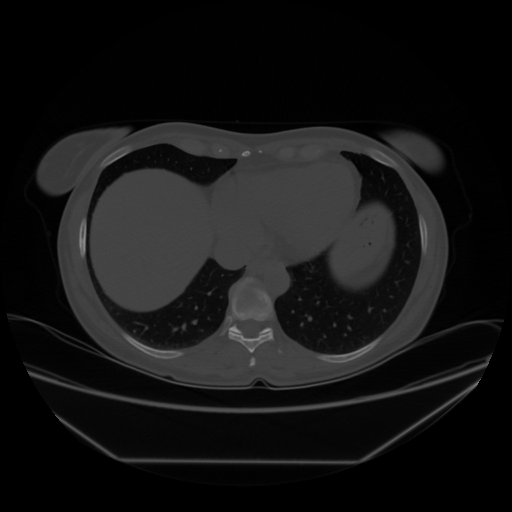

Image Grid

4Γ—3 grid: Rows show different image types (Original NATIVE, Reconstructed NATIVE, Original VENOUS, Generated VENOUS), Columns show windowing techniques (No Window, Lung Window, Mediastinum Window)

Original VENOUS CT scan

Lung window (WL -600, WW 1500 β†’ Low βˆ’1350, High +150)

Mediastinum window (WL 40, WW 400 β†’ Low βˆ’160, High +240)